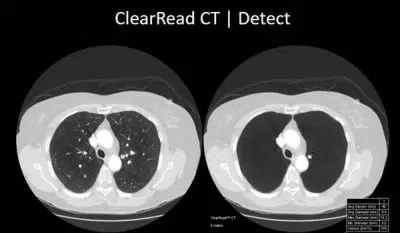

With the COVID-19 pandemic upon us, and the emphasis on chest screening, it made sense for Princess Alexandra Hospital NHS Trust to consider AGFA’s CT AI Package, that included RUBEE and ClearRead CT Algorithm from Riverain Technologies.

Vessel Suppress helping pick up early cancerous nodules

The small perivascular intra pulmonary nodule can be difficult to detect and often can be mistaken for an end on vessel. The AI tool detects these nodules more readily and accurately by “suppressing” the adjoining vessels – thereby picking up potential early cancerous nodules / metastases.